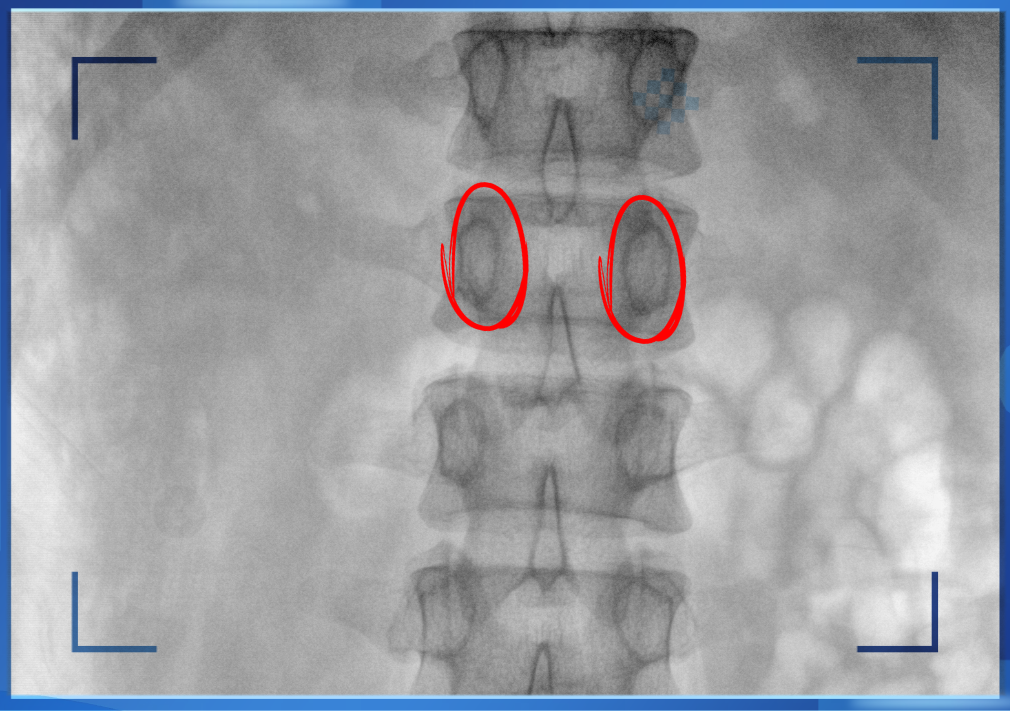

醫(yī)生通常會在“貓眼”里尋找進(jìn)針點(diǎn)和出針點(diǎn),憑醫(yī)生的經(jīng)驗把釘子打在椎弓根里。手術(shù)比較依賴醫(yī)生的經(jīng)驗,萬一出現(xiàn)偏差對病人來講就是毀滅性的打擊。如果在復(fù)雜的手術(shù)中有三維影像的支持,確保釘子精準(zhǔn)的打在椎弓根里,可大大的提高手術(shù)操作的精度。

“貓眼”指的是椎弓根在正位的投影。